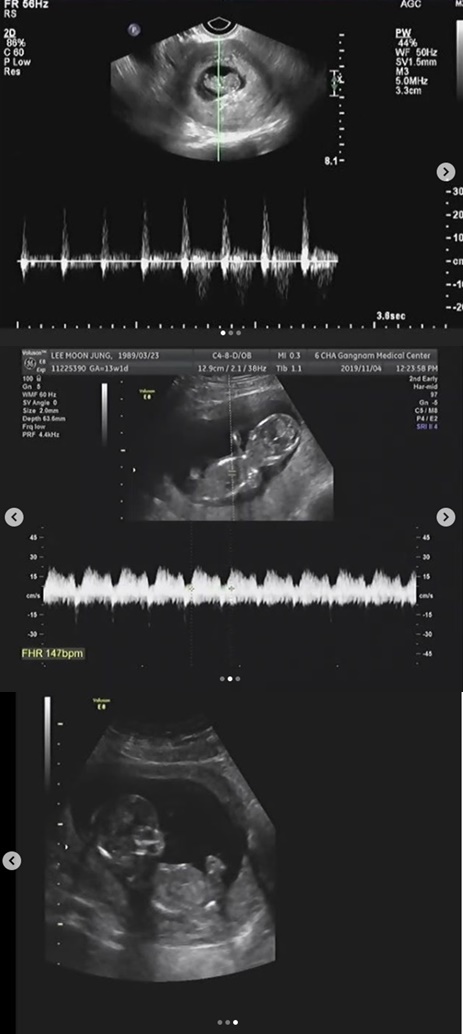

이문정은 13일 오후 자신의 인스타그램에 직접 임신 소식을 전하며 초음파 사진을 공개했다.

이문정은 아기의 태명을 곰젤리에서 영감을 얻어 '꾸미'라고 지었다며 "너무 부족한 엄마가 되진 않을까 염려가 되고 또 앞으로 저의 배우로서의 삶에 찾아올 변화에 대한 두려움도 많지만 조금씩 꾸미와의 만남이 기대가 되고 있다. 이제 안정기에 접어들어서 이렇게 아기 사진으로 소식 전한다"고 말했다.